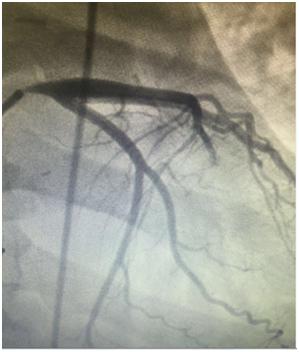

At day 20 after discharge, the patient experienced further episodes of chest pain she was readmitted for acute coronary syndrome coronary angiography showed that the bridge was no functional. Thus, percutaneous coronary angioplasty of the left main coronary artery was performed with implantation of a drug-eluting stent. No other events were reported, the follow up is about four months until now.